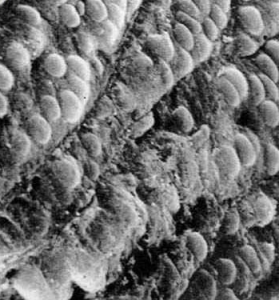

電鏡下,滑面內質網遠較球狀帶為多,常環繞脂滴和線粒體排列,粗面內質網也較發達。細胞排列成單行或雙行的細胞索,由皮質向髓質呈放射狀排列。索之間有少量血竇和少量結締組織。束狀帶細胞分泌糖皮質激素